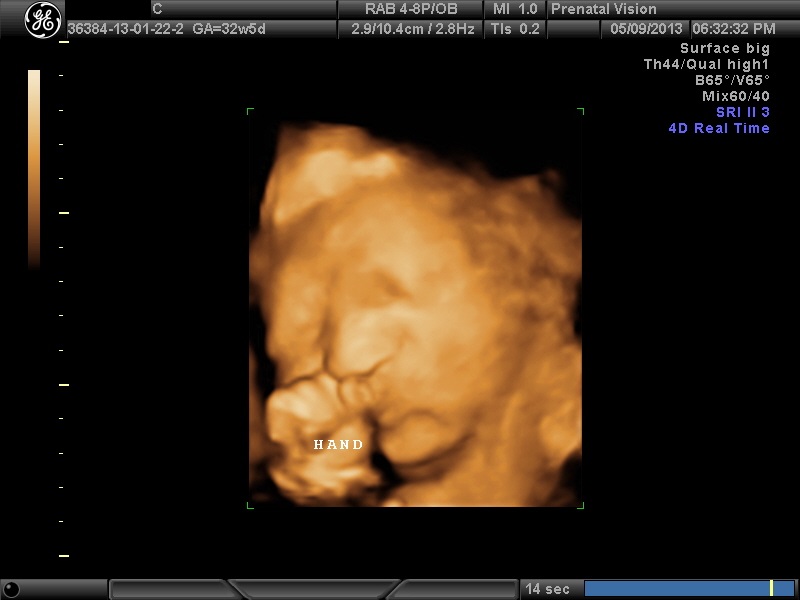

IMAGES_20 May 13, 2013 by Courtney Leave a comment ← Previous Image Next Image → 32w5d Like Loading...